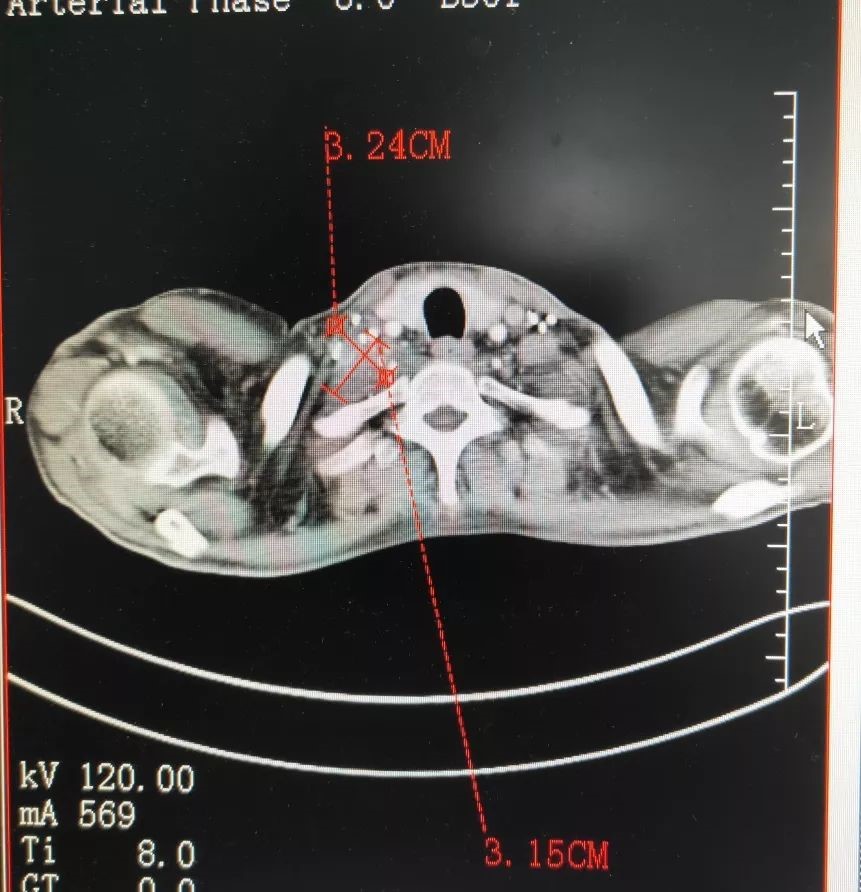

После консультации с экспертами ФУДА, LEE был диагностирован с множественными метастазами в лимфатических узлах cTxNxM1 в двухсторонней шее и средостении и множественными метастазами в легких, что подтверждено МРТ с контрастным сканированием. Лимфатические узлы опухли, они давили на пищевод и вызывали опухание его руки. Врач Лю Шупэн сказал: «Карцинома тимуса с лимфатическими метастазами в средостении имеет высокую степень злокачественности, поэтому трудно проводить хирургическое вмешательство, а рак не чувствителен к химиотерапии. Местное лечение - лучший способ помочь пациенту выжить в течение длительного времени». Поскольку опухоль средостения находится в ключевом положении, и многие опухоли средостения, особенно злокачественные, не могут быть удалены хирургическим путем. Хотя обычная лучевая терапия и химиотерапия, включая гамма-нож, X-нож и т. д., вызывают серьезные побочные эффекты, такие как кардит, васкулит, пневмонию и воспаление пищевода, которые оказывают большое влияние на организм и даже приводят к смерти. Кроме того, многие пациенты отказываются от традиционных методов лечения из-за высокой вероятности рецидива после лучевой и химиотерапии.

После экспертного диагноза врачи выбрали брахитерапию и криохирургию в соответствие с опухолью LEE. Поскольку опухоль находилась рядом с крупными кровеносными сосудами и нервной тканью, неполное удаление средостения обычно сопровождалась с риском. Более безопасно использовать брахитерапию в хирургической области вблизи плечевого сплетения, и брахитерапия может лечить ту часть, с которой нельзя справиться во время криохирургии без повреждения нервной ткани. Поскольку диапазон опухолей был относительно большим, на оставшейся области, которая не была покрыта брахитерапией, были выполнены две криохирургические операции. Криохирургия - самый безопасный метод абляции в минимально инвазивных методах лечения. Он не только защищает крупные кровеносные сосуды, но и оказывает минимальное воздействие на крупные сосуды, пищевод и желудочную трубку.